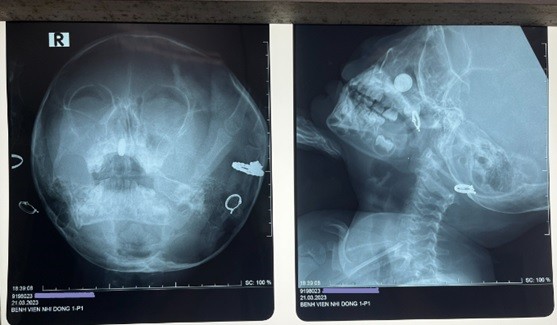

Dị vật trên phim Xquang thẳng - nghiêng của bệnh nhi. Ảnh: Bệnh viện cung cấp

Ngay trong đêm, sau khi tiếp nhận, các bác sĩ đã thăm khám, chỉ định chụp Xquang, kết quả xác định dị vật mũi nghi pin điện tử dạng cúc áo.